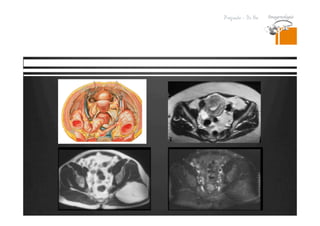

Lesiones isodensas en TC.

RESONANCIA MAGNETICA

DR. JULIO LAMA

Pregrado – Dr Yee

Resonancia

Tomografia